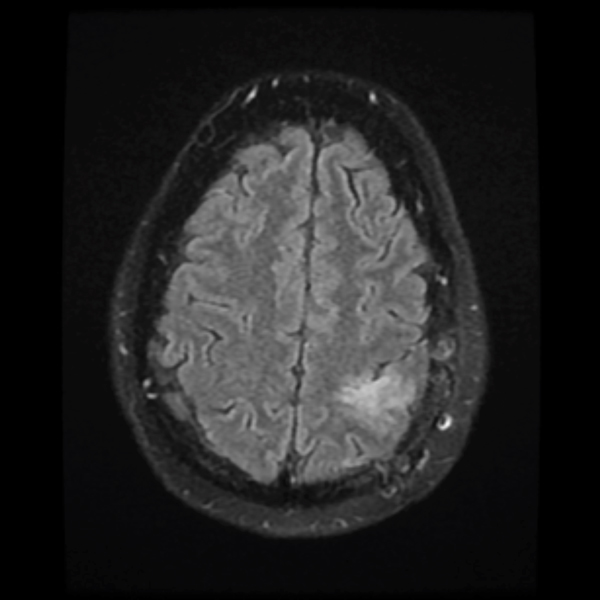

December 2019

Treatment with chemotherapy and radiation under the care of Dr. Grewal resulted in a durable response of the tumor as evident in the post-treatment images.

The patient has returned to work with a resolution of cognitive impairment, has no neurological impairment, and the tumor continues to shrink on each serial MRI.